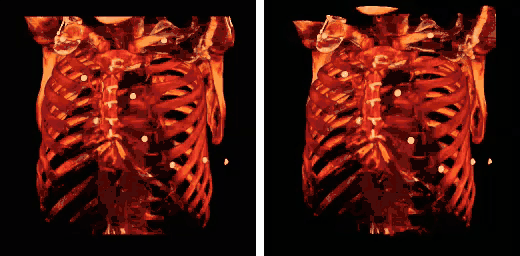

Caja torácica humana - TC (proyección paralela [izquierda] y proyección en perspectiva [derecha]) -